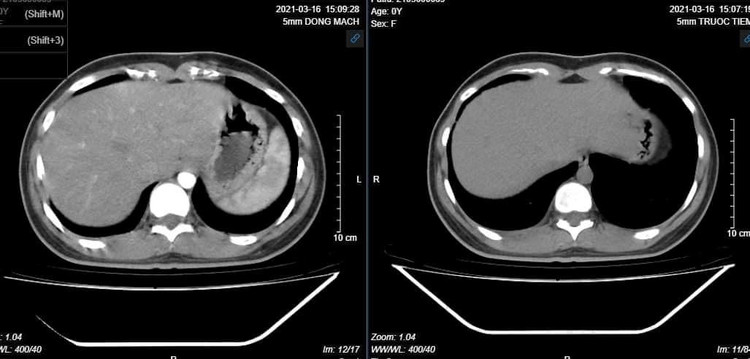

Bệnh nhân nữ (19 tuổi, Hà Nội) vào viện vì đau bụng vùng hố chậu phải ngày thứ 3, đau tăng khi vận động, thở mạnh. Bệnh nhân ra ít dịch âm đạo mùi hôi. Kết quả CT cho thấy, bao gan dày ngấm thuốc mạnh thì động mạch, phần phụ phải tăng kích thước, thâm nhiễm mỡ xung quanh, vài hạch mạc treo, phúc mạc dày và ngấm thuốc sau tiêm. Bệnh nhân được chẩn đoán Hội chứng Fitz-Hugh-Curtis – FHCS (PID + perihepatits) và được điều trị nội khoa.

Bao gan dày, ngấm thuốc mạnh thì động mạch.

Chụp cắt lớp vi tính ổ bụng có tiêm thuốc cản quang là một phương pháp có giá trị cao trong chẩn đoán với các biểu hiện dày bao gan, dày phúc mạc khu trú...